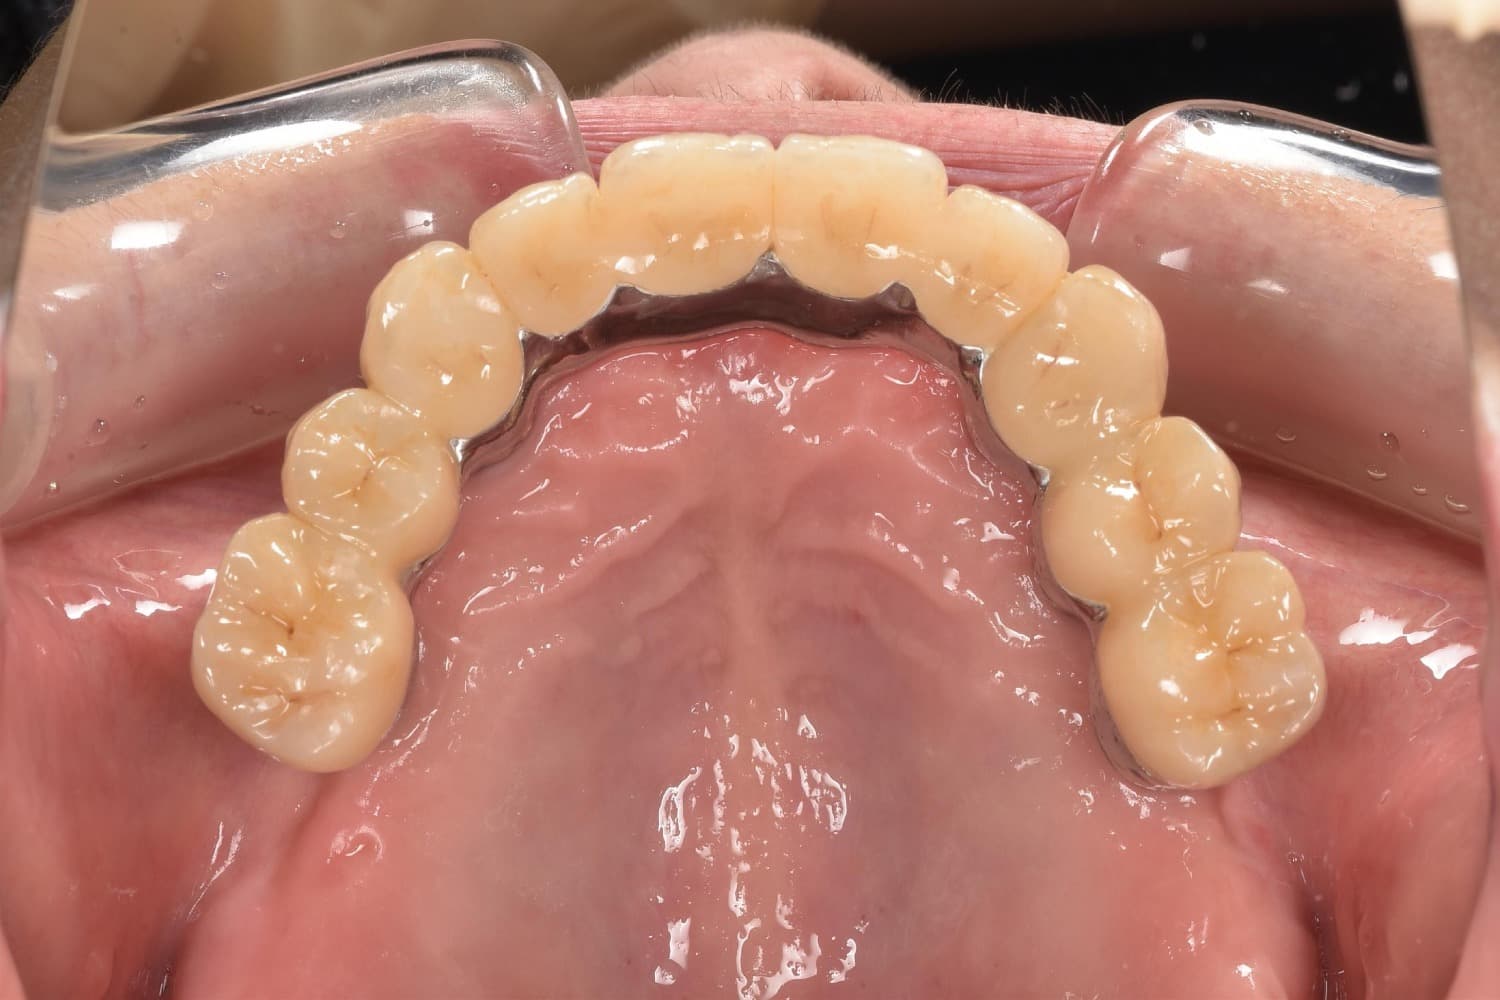

上顎のインプラント治療

Before

After

上顎全ての歯が保存不可能。5本のインプラント埋入を行いました。 費用や清掃性を考慮し、短縮歯列での治療としました。 治療後は見た目も満足され、何でも食べることが出来ると、患者様も非常に喜ばれています。

年齢

60代

性別

女性

主訴

しっかり咬めるようになりたい。見た目も綺麗にしたい。

治療期間

6ヵ月

治療回数

12回

費用

上顎全て:約300万円

副作用・リスク

術後の腫れや痛みの可能性、インプラントの骨結合不良、清掃不良による治癒不全